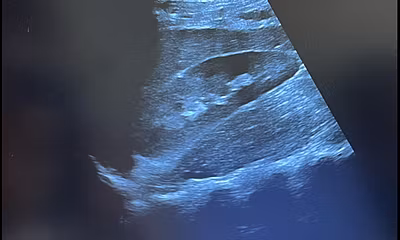

Gleichzeitig fand ich es faszinierend, an so vielen medizinischen Situationen beteiligt zu sein. Man brachte mir bei, wie man einen Ultraschall durchführte, und sogleich durfte ich damit die Patienten untersuchen.